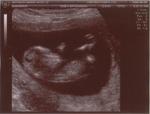

12 sem écho-3 bébé 2

Date : 06/10/2006 Affichages : 1359